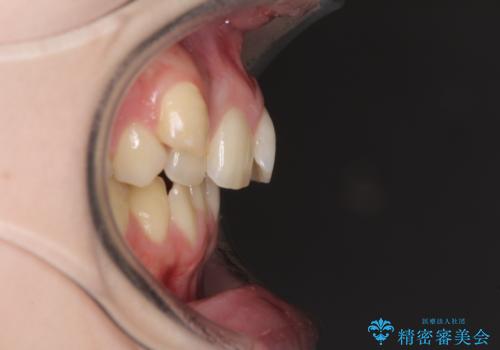

- 著しい八重歯を気にして来院された患者様です。

片側の八重歯であり上顎の正中がずれていたため、上顎左右第一小臼歯2本を抜歯して排列することとしました。